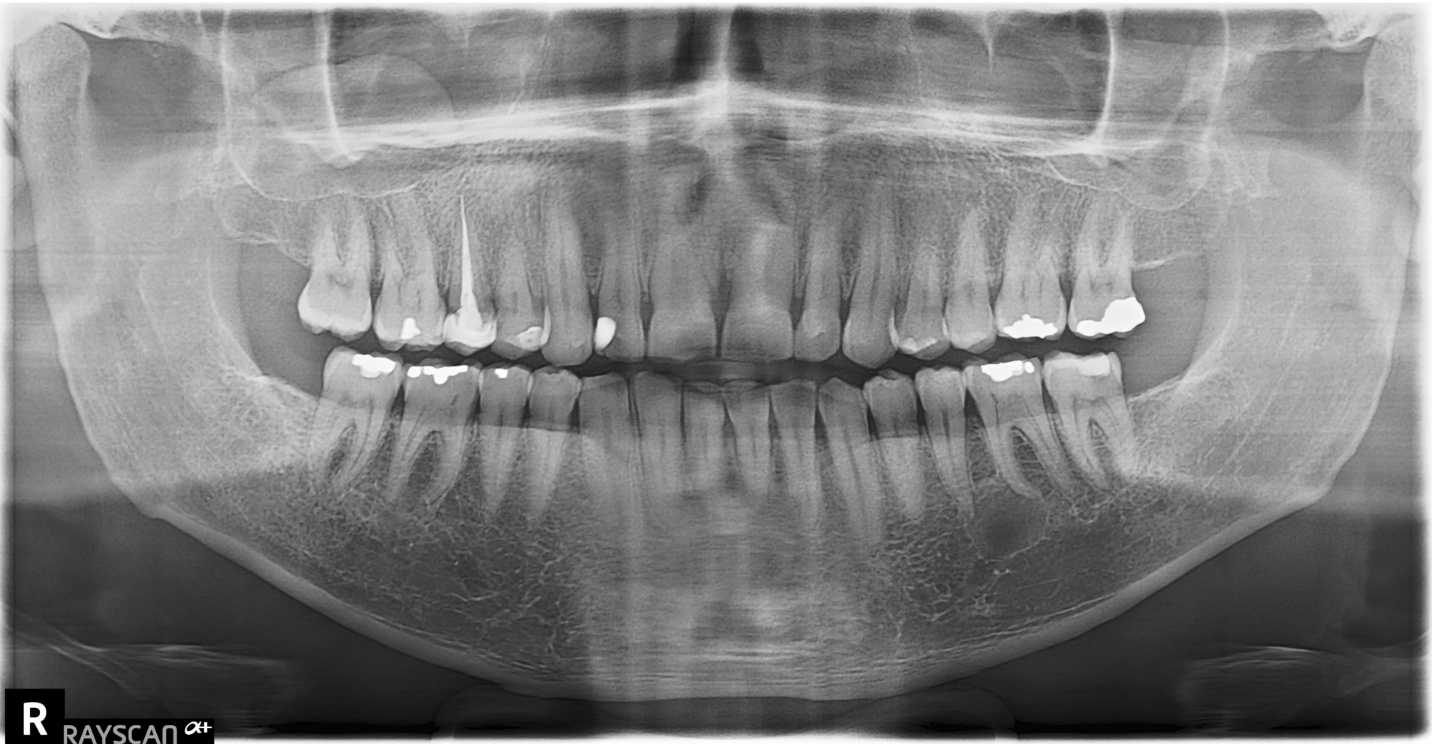

A 40-year-old male complains of pain in the mandibular left first molar region. A pantomograph was made.

Radiographic findings: A radiolucent area associated with the apical regions of the mandibular left first molar. The entity has well-defined thin corticated borders and has a hydraulic appearance. The first molar has recurrent caries in close proximity to the pulp chamber.

Interpretation: Radicular cyst

Other Incidental findings: There is a dome-shaped radiopaque mass in the floor of the right maxillary sinus. The entity has the density of soft tissue; the appearance is consistent with a mucus retention phenomenon (pseudocyst). No treatment is necessary for this condition.